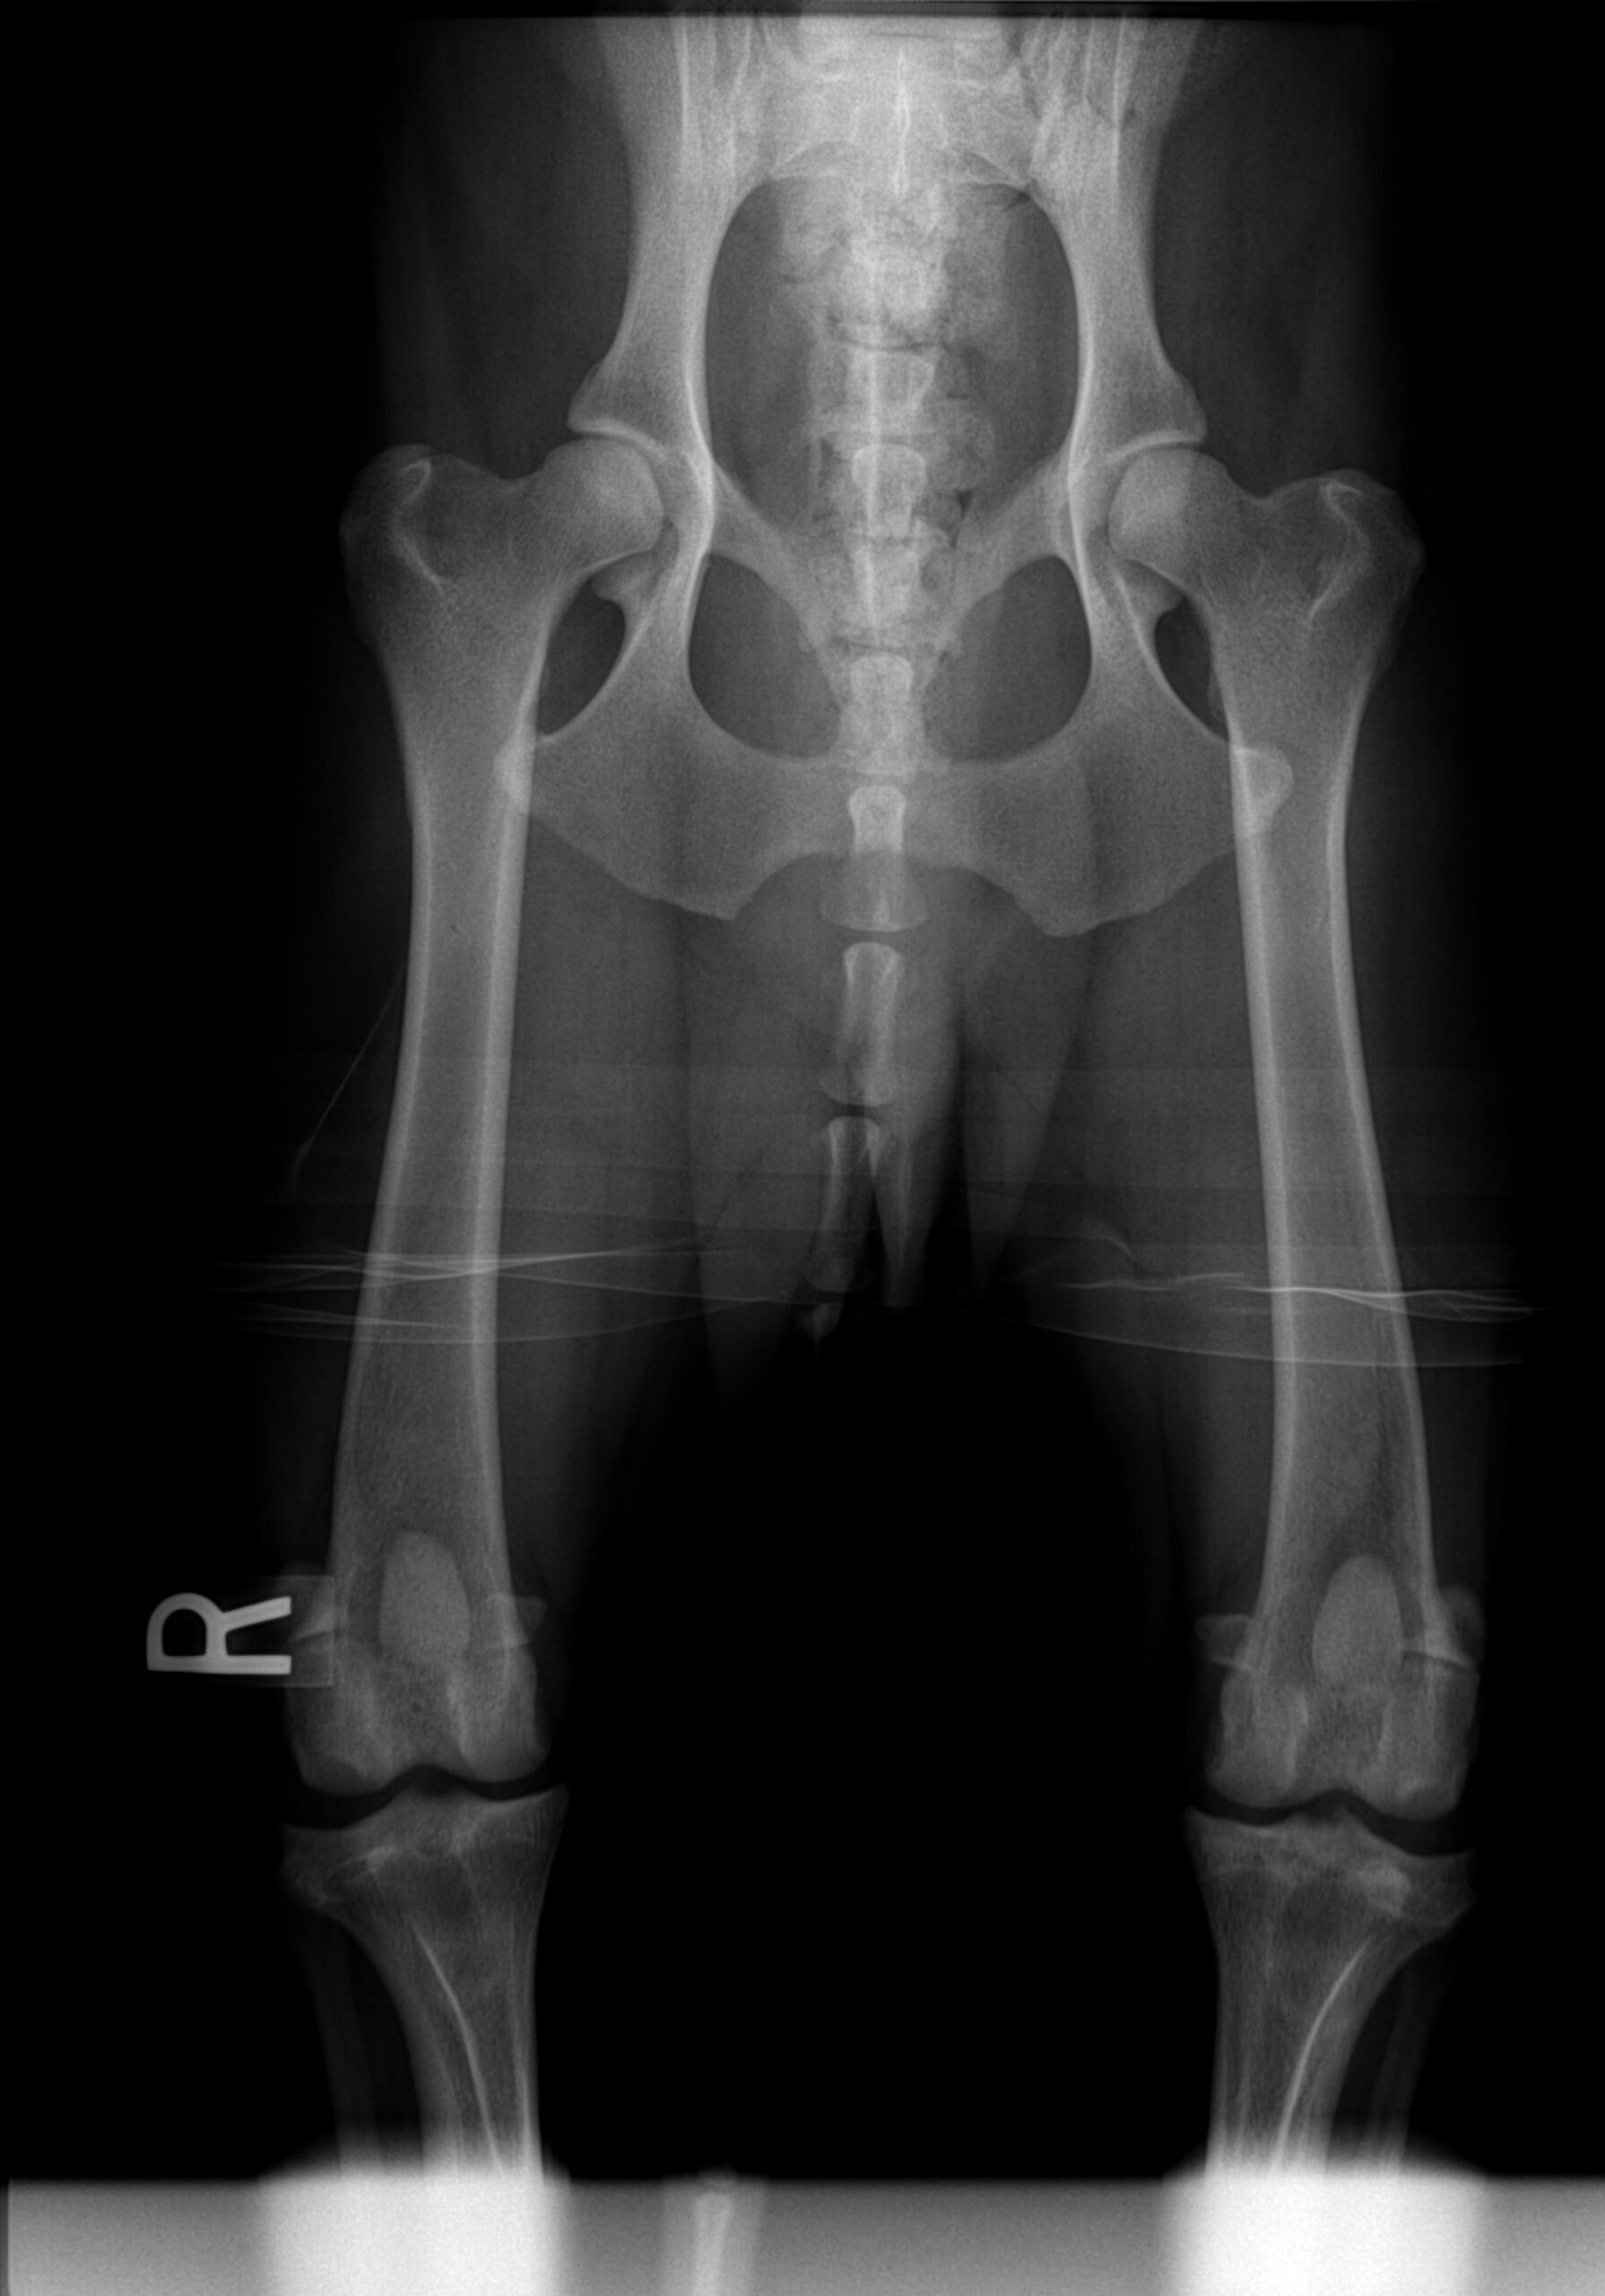

Паностеит у собак

Паностеит у собак 118 фотографий